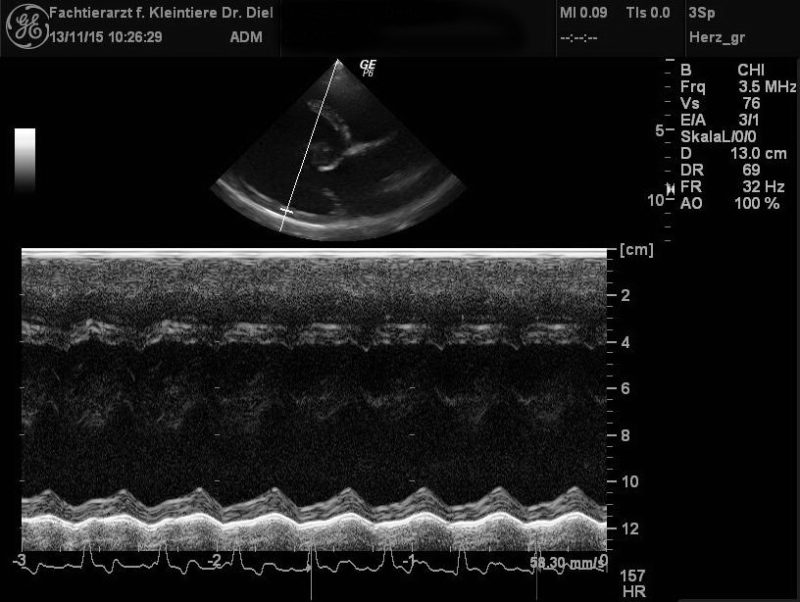

Ein Röntgenbild kann jedoch höchstens Hinweise auf Herzerkrankungen geben – allein genügt es nicht für eine sichere Diagnose. Ich habe daher das Herz noch einmal genauer mittels Ultraschall untersucht. Diese sogenannte Echokardiographie zeigte bei Momo eine deutlich vergrößerte linke Herzkammer mit sehr dünnen Herzwänden und einer stark verminderten Kontraktilität (die Herzkammer zieht sich also deutlich weniger stark zusammen als normalerweise). Daneben war auch der linke Vorhof vergrößert. Ich musste daher als Diagnose eine Dilatative Kardiomyopathie (DCM) feststellen.